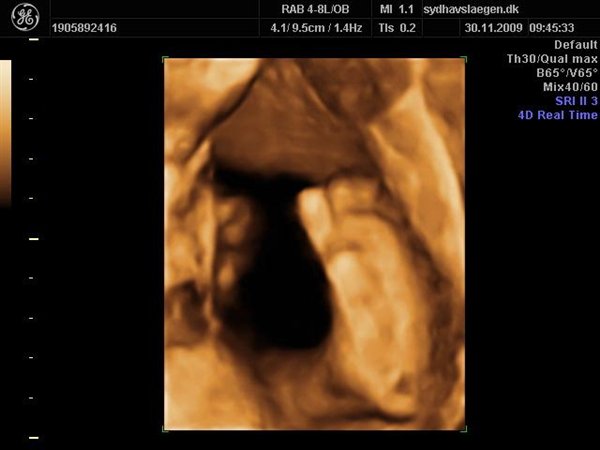

Da jeg snakkede med hende i dag sagde hun at fra uge 27 til og med uge 31 var det bedste tidspunkt at få det gjort....

Vi skal give 1400 kr for 45 minutters total gennem scanning, hvor hun fortæller, undersøger babyen fra top til tå, laver vægtskøn også får vi billeder og dvd med hjem.... Og ja det er da mange penge, men min forlovede har haft en masse vikar timer den her mdr, også sagde han at han syntes vi skulle bruge de penge på noget vi normalt ikke ville have gjort. Han sagde egentlig at jeg kunne gå ud og shoppe for dem, men jeg har termin om ti uger, så gider ærlig talt ikke bruge penge på nyt graviditets tøj, så hellere det her som vi egentlig havde valgt fra pga prisen, men som vi begge to rigtig gerne vil....